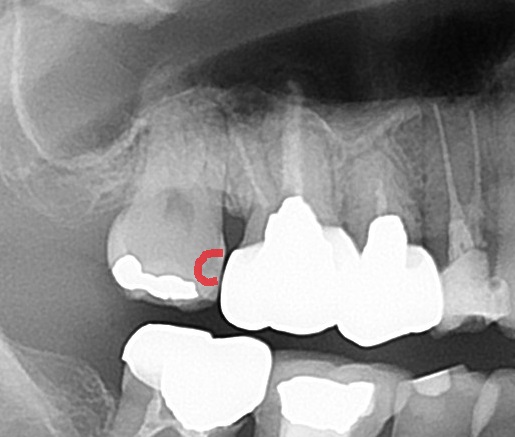

またレントゲン写真(エックス線写真)でけんさすると、

このように歯の内部が見えてきます。

よく見ると、

手前との間に、黒く虫歯の影が見えます。

つまり、詰め物をしたところとは別に!